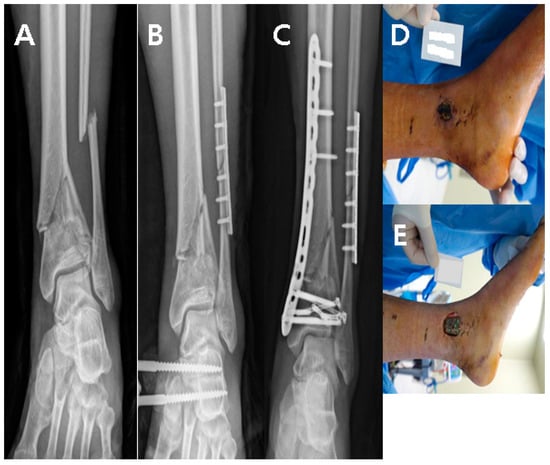

A 22-year-old man visited our emergency center with a pilon fracture caused by a 2 m fall down accident. Radiological examination revealed severe shortening of the tibial joint surface, and emergency surgical treatment using external fixation was performed. Two weeks later, conversion using the MIPO technique for tibia and plate fixation in the fibula was performed (Figure 1A–C). One month after internal fixation, soft tissue defects and metal plate exposure were observed on the medial side of the left ankle (Figure 1D,E).; therefore, a reverse sural artery flap was performed (Figure 2A–D). The size of the flap was 2 × 3 cm2, and the length of the flap pedicle was 7 cm. The donor site was sutured, and the donor site and flap survived without complications at the final outpatient follow-up.

Figure 1. (A) Pilon fracture by 2 m F/D. (B) For the two-stage operation, EF was done. (C) Conversion operation was performed using the MIPO technique. (D,E) One month after MIPO, skin defect and plate exposure occurred.